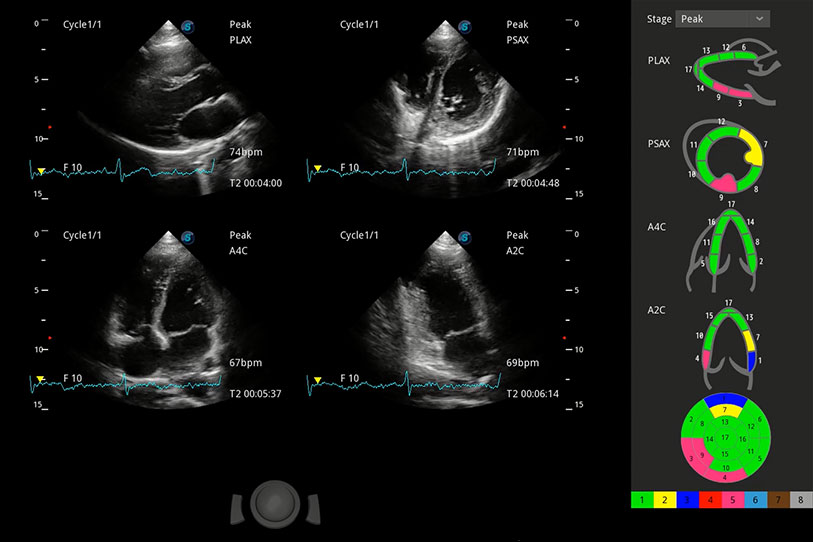

能够基于左心室壁追踪和辛普森法,自动计算射血分数,支持多个可移动点描迹,与手动测量相比,极大节省了动物医生的时间和精力。

具备多种协议可选,同时支持17阶段划分法和专业的SE报告。